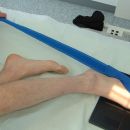

Lagerung

Patient sitzt auf dem Tisch, Fuß plantar aufgestellt (evtl. auf einem Stuhl), bei verkrümmten Zehen mit Zellstoff unterpolstern.

Lagerung

Pat. sitzt auf dem Tisch, Fuß mit der medialen Seite aufliegend, die anderen Zehen mit Band zurückziehen.

1. Möglichkeit: Patient liegt auf dem Rücken, das Sprunggelenk wird zum Kopf angezogen. Mit einem Band werden die Zehen in Richtung Knie gezogen.

2. Möglichkeit: Patient liegt auf dem Bauch, der Fuß wird so aufgestellt, dass die Plantarseite der distalen Zehenglieder an die Kassette gelehnt wird. Das Sprunggelenk steht im rechten Winkel, die Zehen sind in Dorsalflexion.